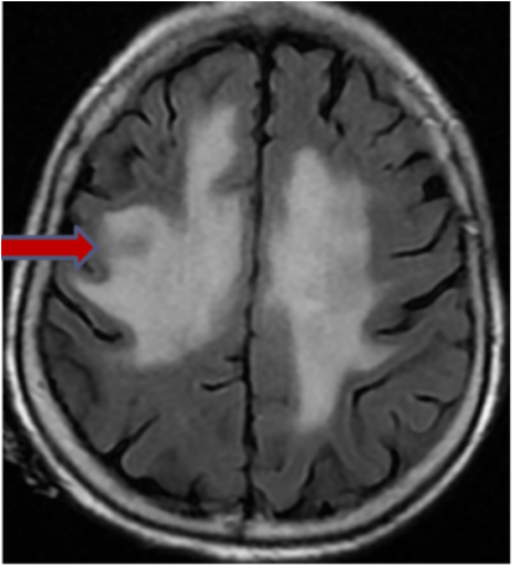

磁共振弥散成像DWI(2025-05-08):颅内多发异常信号,病变多位于深部脑白质及核团区,较前范围明显增大,结合病史,不除外转移可能。

图5 患者颅脑MRI表现

感染控制后,于2025-04-24鞘内注射甲氨蝶呤+阿糖胞苷+地塞米松,于2025-04-26予利妥昔单抗+维泊妥珠单抗+依托泊苷+匹妥布替尼200mg qd方案化疗,期间复查颅脑核磁提示脑部病变范围较前增大,考虑肿瘤进展累及中枢,于2025-05-15予甲氨蝶呤治疗,因输注后出现高血压急症,遂暂停甲氨蝶呤输注。

排除禁忌症后于2025-5-17、2025-6-7予RMT-Pola(利妥昔单抗+甲氨蝶呤+替莫唑胺+维泊妥珠单抗)+匹妥布替尼方案。分别于2025-6-30、2025-7-21予RMT-Pola(利妥昔单抗+甲氨蝶呤+塞替派+维泊妥珠单抗)+匹妥布替尼方案。治疗后患者症状体征较前改善:神志逐渐好转,现已意识清醒;瞳孔等圆等大,对光反射灵敏;咳嗽、咳痰较前减轻;左侧肢体肌张力可,肌力Ⅲ级,右侧肢体肌张力高,肌力Ⅱ级。颅脑DWI见肿瘤病灶较前缩小,PET-CT提示疗效达PR。